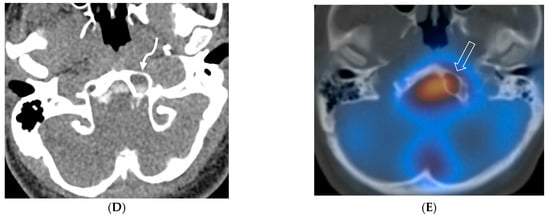

Figure 8.

Sagittal T1 (A), post axial T1 (B,C), axial CT myelogram (D) and technetium 99 m DTPA SPECT-CT (E): 16-year-old with Gorham’s disease. There is cerebellar tonsillar herniation and decrease in prepontine cisterns (white arrows). Significant increase in the size of the venous sinuses (dashed arrow). Diffuse pachymeningeal enhancement is seen (black arrows). Cystic-appearing foci at the skull base are in keeping with lymphangiomatosis with contrast pooling into the lytic lesion (curved arrow). Abnormal radiotracer extravasation in the left clival region correlating with lytic lesion (open arrow). Features are in keeping with intracranial hypotension secondary to CSF leak.